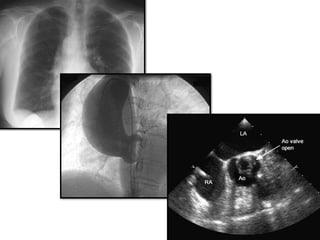

2D - Apical five chamber view

2D – Suprasternal view

2D - Apicalfive chamber view

• 16.